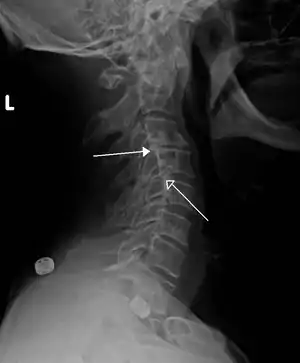

A retrolisthesis is a posterior displacement of one vertebral body with respect to the subjacent vertebra to a degree less than a luxation (dislocation). Retrolistheses are most easily diagnosed on lateral x-ray views of the spine. Views where care has been taken to expose for a true lateral view without any rotation offer the best diagnostic quality.

| Grade 1 retrolistheses of C3 on C4 and C4 on C5 | |

Since the vertebral body in a retrolisthesis moves in a posterior direction, the grading used for spondylolistheses is of little use. It is however useful to divide the anterior to posterior dimension of the intervertebral foramina (IVF) (4) into four equal units. A posterior displacement of up to ¼ of the IVF is graded as Grade 1, ¼ to ½ as Grade 2, ½ to ¾ as Grade 3, ¾ to total occlusion of the IVF as Grade 4. Alternatively, a measurement of the amount of displacement can also made by measuring the bone displacement in millimetres.